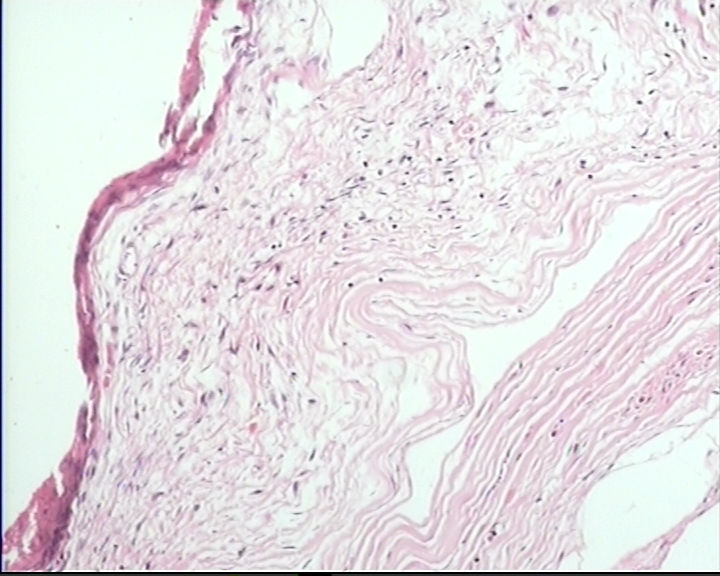

这一类型的卵巢囊肿该怎么发?

剖宫产时卵巢上面剥离下来的,7×6.5×2cm,囊壁菲薄,内容淡黄色清亮液体,内壁光滑

卵巢囊肿图2

名称:图2

仔细找找,如果确实没有明确的被覆上皮就报单纯性囊肿。

单纯囊肿。未见明确上皮成分,良性。

同意单纯性囊肿,没有被覆上皮。

未见被覆上皮,单纯性囊肿。